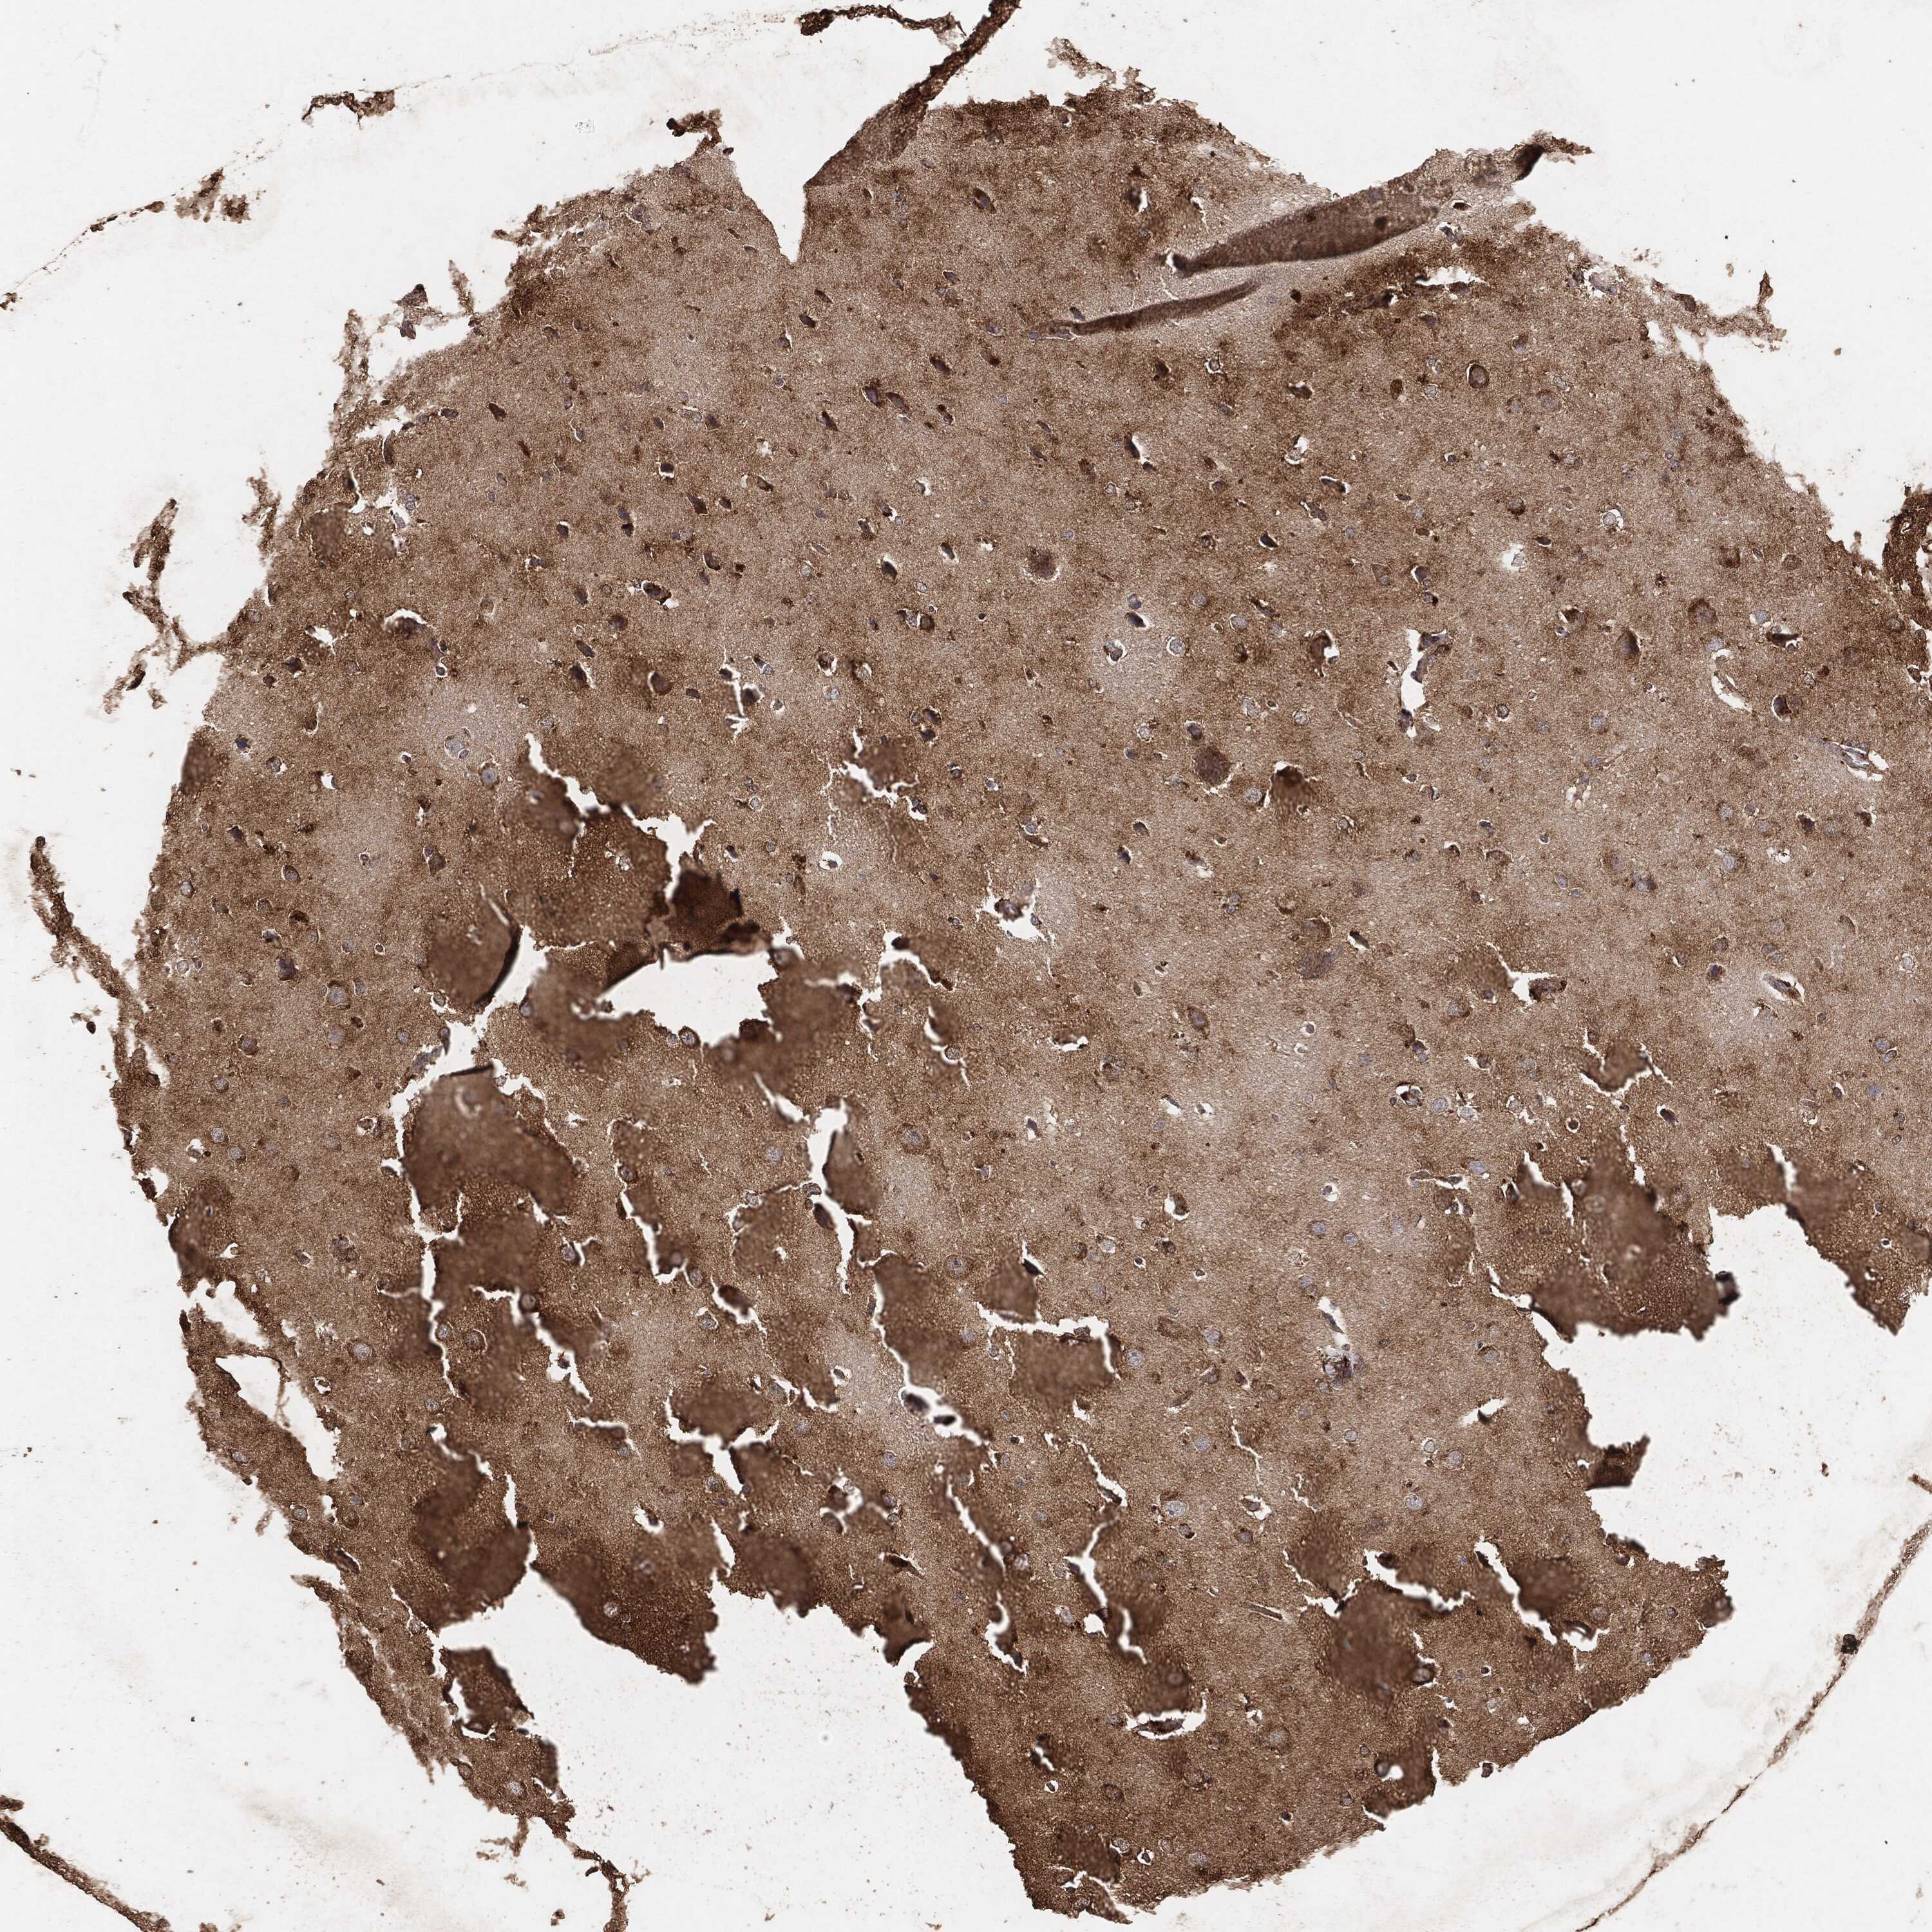

GLIOMA - Protein expressioni

A mouse-over function shows sample information and annotation data. Click on an image to view it in a full screen mode. Samples can be filtered based on level of antibody staining by selecting one or several of the following categories: high, medium, low and not detected. The assay and annotation is described here.

Note that samples used for immunohistochemistry by the Human Protein Atlas do not correspond to samples in the TCGA dataset.

Antibody stainingi

Antibody staining in the annotated cell types in the current human tissue is reported as not detected, low, medium, or high, based on conventional immunohistochemistry profiling in selected tissues. This score is based on the combination of the staining intensity and fraction of stained cells.

Each image is clickable and will lead to virtual microscopy that enables deeper exploration of all samples and also displays staining intensity scores, fraction scores and subcellular localization as well as patient and tissue information for each sample.

Glioma, malignant, High grade

Glioma, malignant, Low grade

Glioma, malignant, NOS